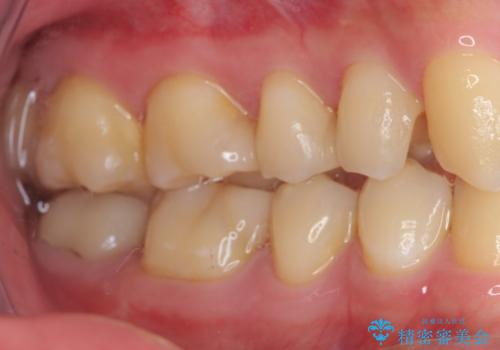

詰め物が外れた セラミックインレー修復

- 以前治療した詰め物が外れてしまい、冷たいものがしみることを主訴として来院された患者様です。

むし歯がないことを確認し、セラミックインレーにて修復するととしました。

適合の良いセラミックインレーの装着により、冷たいものがしみる症状はなくなりました。